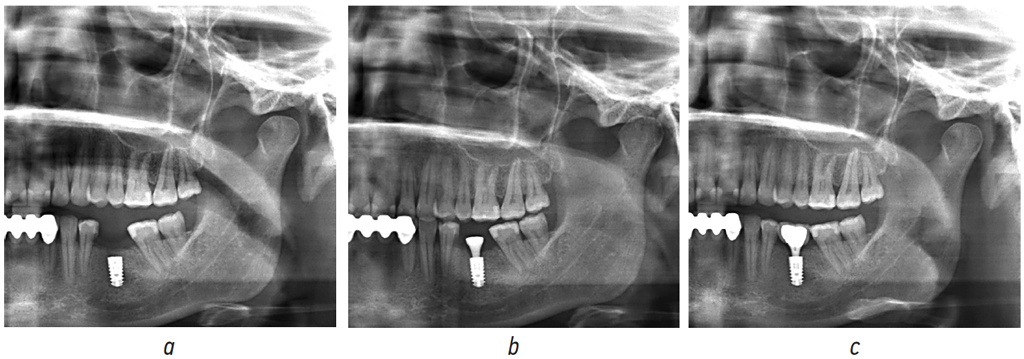

Для дальнейшего анализа исследования были разделены на группы: КЛКТ, ОПТГ, RVG (радиовизиография) (рис. 2).

Рис. 2. Различные виды рентгенологических исследований одного и того же пациента: а — конусно-лучевая компьютерная томография; b — ортопантомография; с — радиовизиография

Fig. 2. Types of X-ray examinations of the same patient: a, cone-beam computed tomography; b, orthopantomography; c, radiovisiography